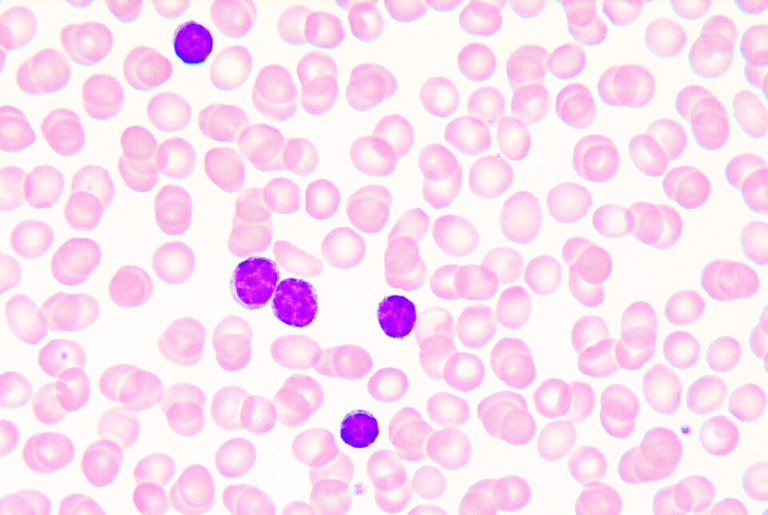

· New mechanistic study in Science Translational Medicine identifies Epstein-Barr virus as a potential trigger of the autoimmune disease systemic #lupus erythematosus